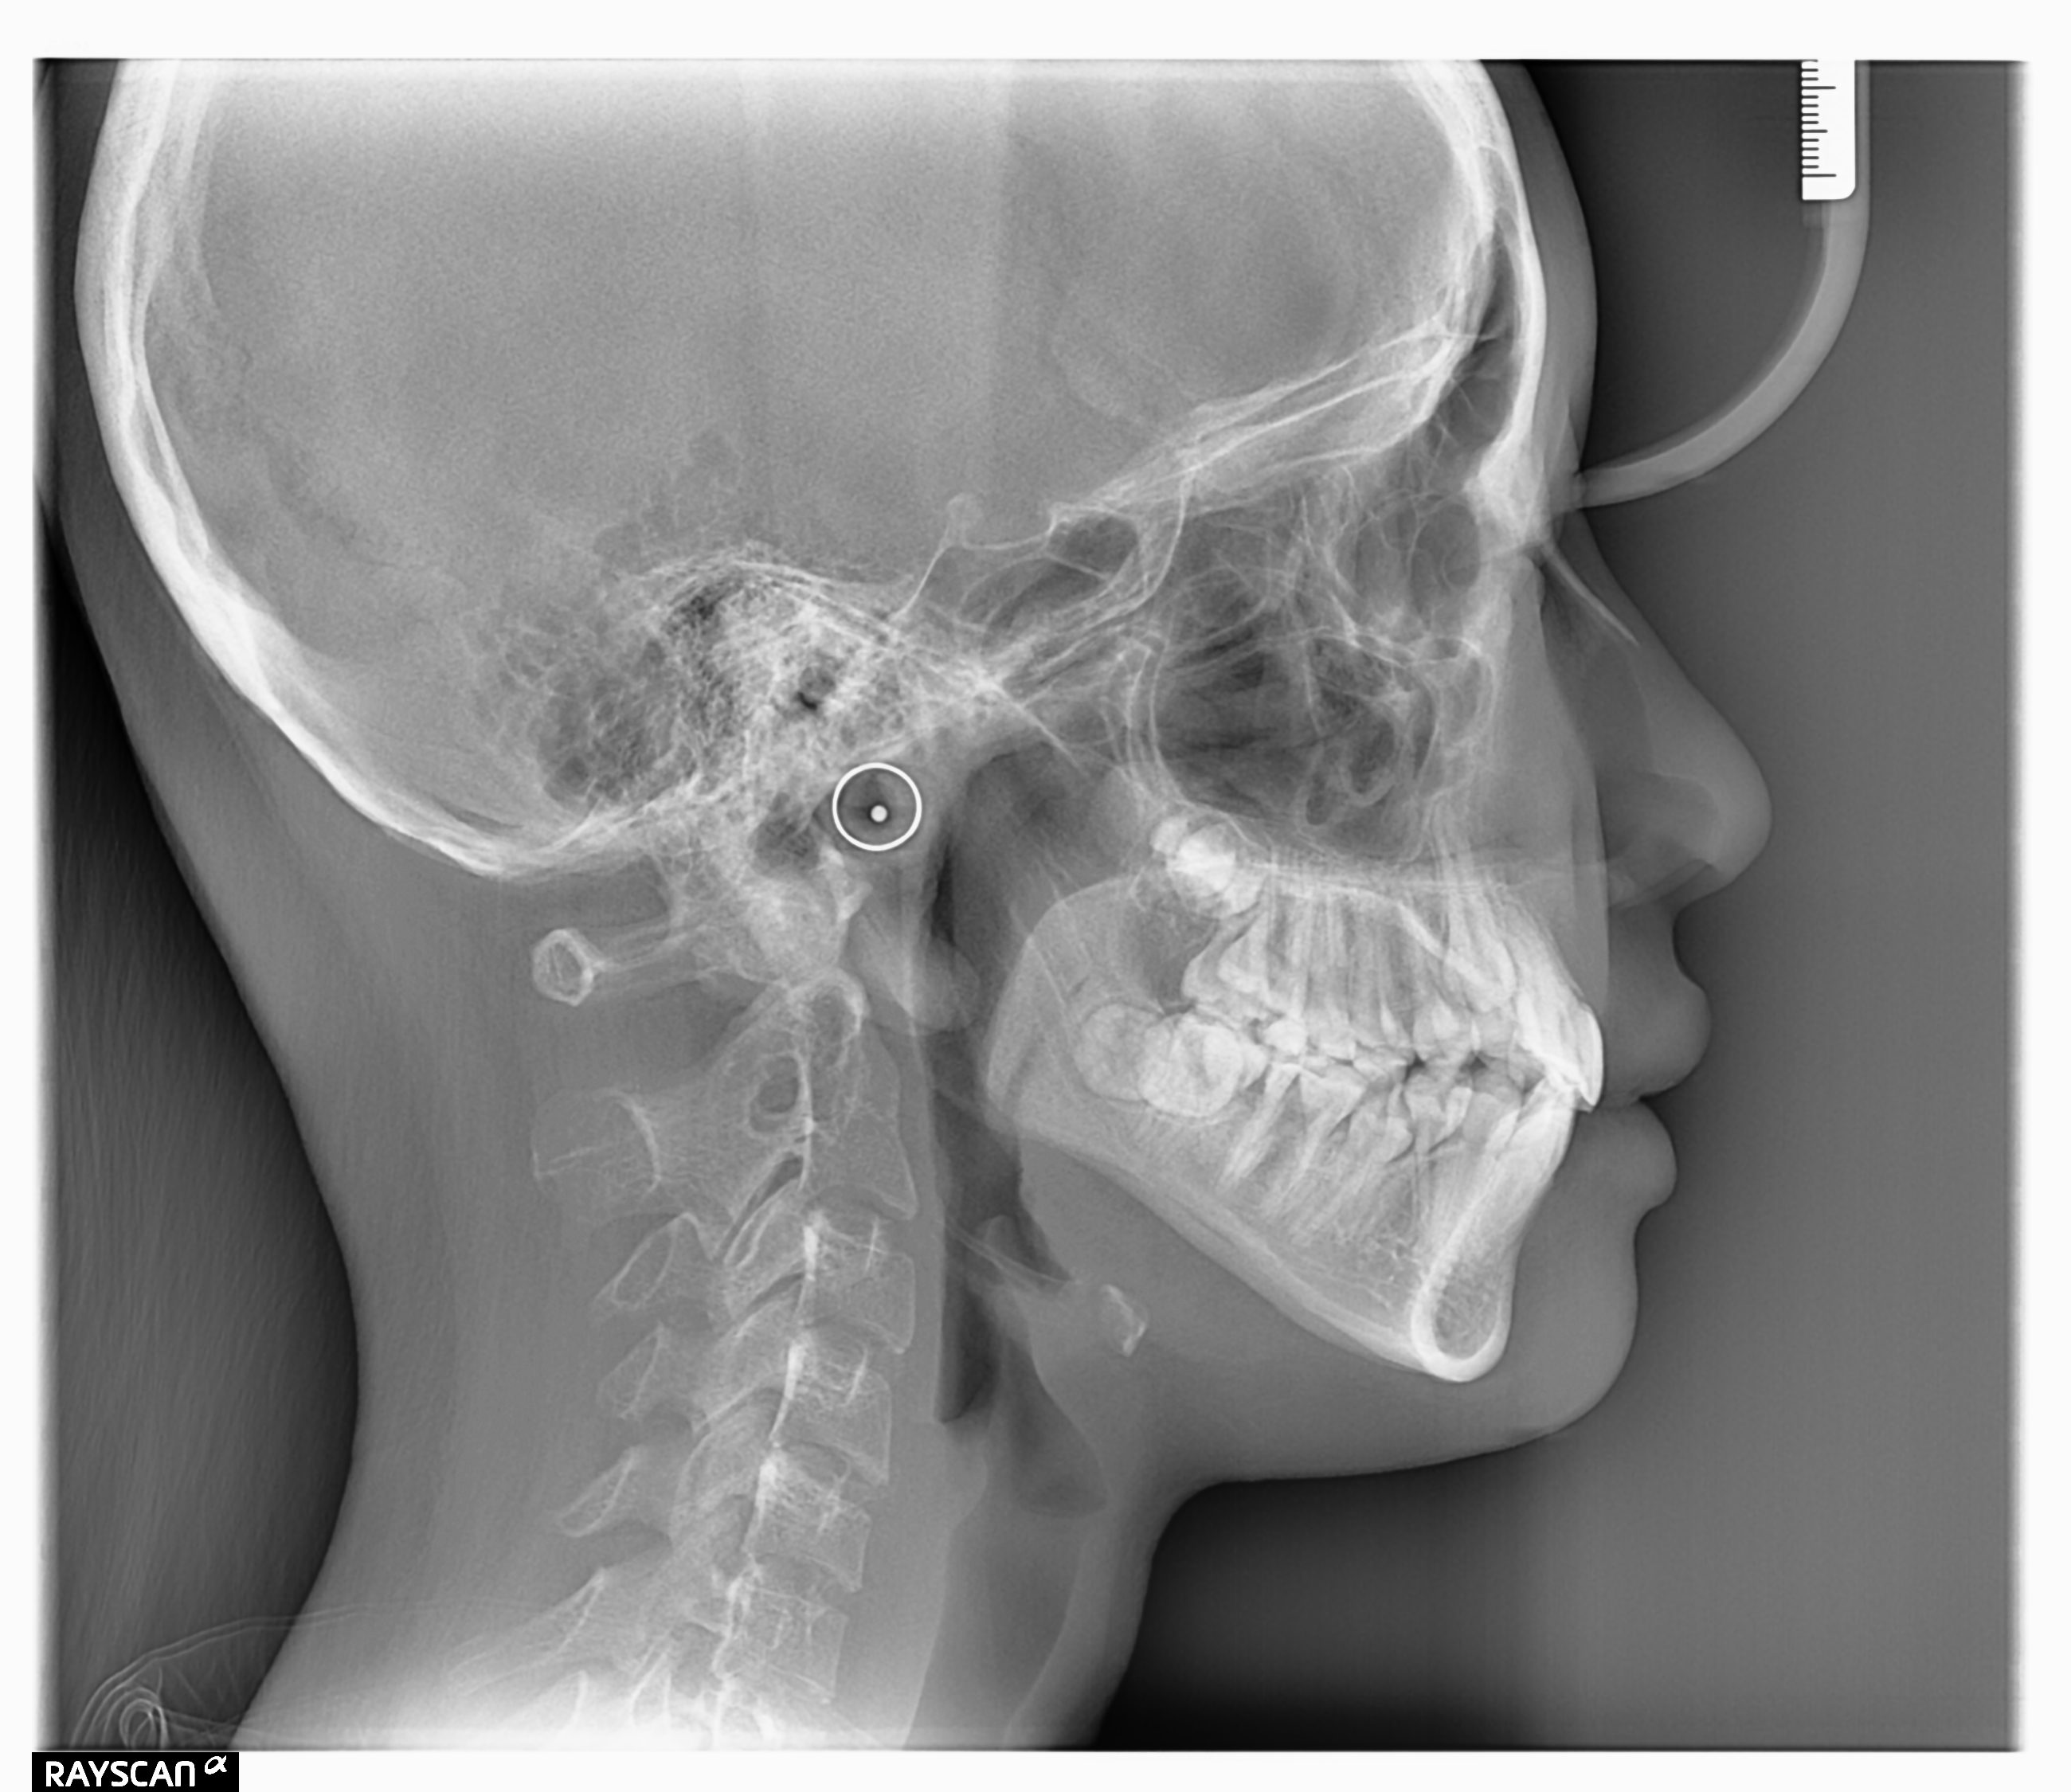

Edit Record Check our patient data records. Add patient information Patient Info Profile picture Last Name First Name Middle Name Birthdate Age Street Barangay City Country Zip Code Contact number Email Procedure 11/28/23- consultation for Braces, OP, X-ray 12/02/23- LC #36 Buccal, #46 Buccal, #34 Buccal Upper Installation of PSL- 14 Thermal NiTi 12/19/23- Installation of Lower Brackets note: No Bracket Installed in #36, #35 02/24/24 OP 1st Adj 16niti -L #36 and #46 for molar band #45 lingual mitton 05/07/24 #36 installed #46 installed button on #35 14 NITI U/L Occclusal pads on #36/46 07/04/24 adj laser canine 09/13/24 adj 01/18/25 adj 18 NITI lower 03/22/25 elastic fox U45 to 5 L(R) U45 to 5 L (L) xray #23/35 activate open coil spring 07/12/25 #23 for retraction(L) chipmunk #23 to #34, #24 to #35 11/15/25 adjustment gingivectomy on #23 placement of bracket on #23 01/21/26 #1 re-attached #45 #18 niti u chipmunks elastic 3.5oz #23 to #34-33 02/25/26 Reattached #45 04/07/26 adjustment File file_0001_4.jpg File 2 file_0001_1_3.jpg File 3 carmelle_perez.jpg File 4 File 5 File 6 File 7 File 8 File 9 File 10 File 11 File 12 File 13 File 14 File 15 File 16 File 17 File 18 File 19 File 20 Retain Record Retain Record Yes No Save Your Changes